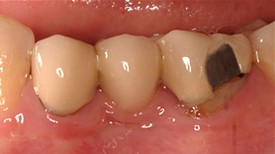

Before: 3 Unit bridge with chipped porcelain molar (supporting metal showing on molar tooth), poor enamel color match to patient’s natural teeth, and poor fit around the patient’s gumline.

After: Replaced Bridge with an All Porcelain Bridge. The new bridge now also matches the patient’s natural tooth color and was designed to properly fit around the gumline. Proper fit aids in decreasing decay and the ease of the patient’s ability to clean around a bridge.